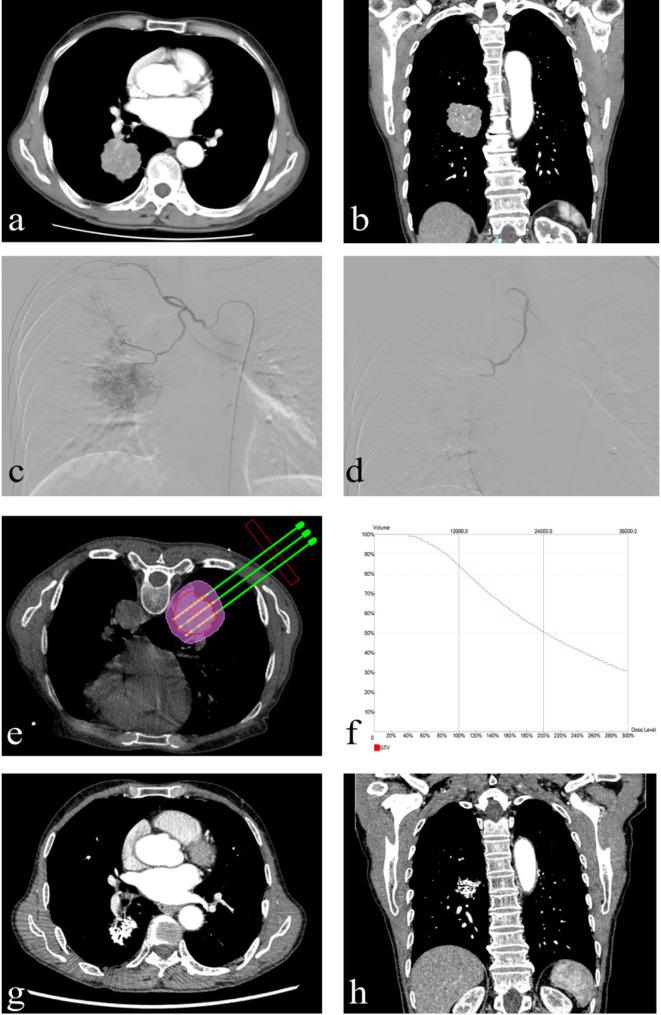

Bronchial arterial chemoembolization/infusion combined with iodine-125 brachytherapy in advanced non-small cell lung cancer: a promising salvage therapy after standard treatment failure.

To evaluate the efficacy, safety and optimal intervention timing of bronchial arterial chemoembolization/infusion combined with iodine-125 brachytherapy for advanced non-small cell lung cancer after standard treatment failure.

From January 2019 to April 2024, the eligible patients with advanced non-small cell lung cancer after standard treatment failure received bronchial arterial chemoembolization/infusion combined with iodine-125 brachytherapy, were included in this retrospective study. Objective response rate, disease control rate, progression-free survival, overall survival and adverse events served as the main indicators of assessment. According to the intervention timing of intervention for this combination therapy, they were divided into the early intervention subgroup and the late intervention subgroup. Statistical analyses were performed using R software (version 3.5.3).

A total of 45 patients with the median age 66 years (11 women) were enrolled in this study. The objective response rate of three months after the combination therapy was 71.11% and disease control rate was 95.56%. The median progression-free survival of this cohort was 12 months and the median overall survival was 20 months. The progression-free survival (15.5 vs. 9 months, P = 0.007) and overall survival (27.5 vs. 15 months, P < 0.001) in the early intervention subgroup was significantly better than that in the late intervention subgroup. No severe complications occurred.

For advanced non-small cell lung cancer after standard treatment failure, the combination of bronchial arterial chemoembolization/infusion and iodine-125 brachytherapy is a promising salvage therapy with good efficacy and safety.